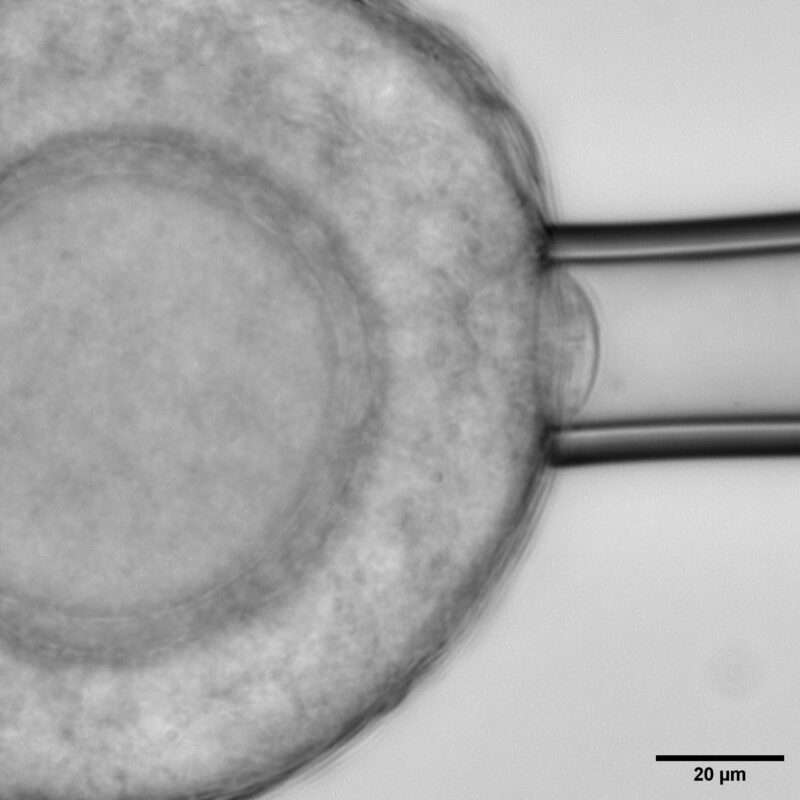

Micropipette aspiration on the follicle surface to measure effective follicle surface tension.

Using young mouse ovaries as a model, the researchers found that theca cells, are far from passive. These spindle-shaped cells at the follicle’s outer boundary are highly contractile, generating measurable compressive stress that regulates the follicle’s internal mechanics. By combining biophysical approaches like atomic force microscopy, micropipette aspiration, and laser ablation, with perturbations and live imaging; the team quantified changes in theca cell and tissue mechanics that proved to be important for regulating follicle morphogenesis.